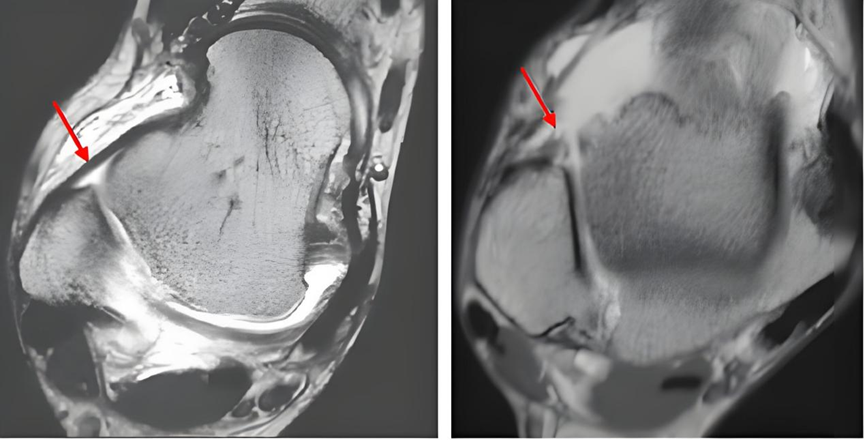

图10:左图为正常距腓前韧带(箭头所示),右图为距腓前韧带断裂(箭头所示)

图19:左图为正常距腓前韧带(箭头所示),右图为距腓前韧带增厚(箭头所示)